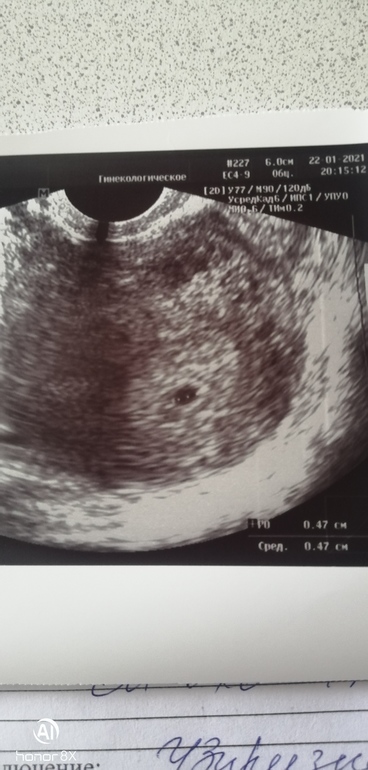

Первое узи и посещение гинеколога🤩🐣

УЗИ, КТГ, доплерСегодня с утра что то начала тянуть поясница, собралась с духом и записалась на консультацию к гине+узи пошла в платную, к той кого знаю и доверяю, врач меня сразу узнала по прошлой зб, сразу посмотрела на кресле, сказала все впорядке-матка увеличина как надо, выделения нормальные, шейка отличная🙄Дальше узи-мою икринку сразу нашли🙈ей все понравилось-жёлтое тело отличное, эндик суппер, все совпадает со сроками🙏По поводу хгч вообще она не заморачивалась когда я ей показала рез-ты, сказала что все отлично и вообще при нормальной беременности и если это не двойня, он не должен увеличиваться в 3-4 раза как я думала, в общем сказала больше хгч не сдаем, это не к чему🤔Велела продолжать пить дюф в обязательном порядке ещё сказала начинать принимать магний-что б успокоить мои истеричные нервы😃Пока на этом все, сказала приходить через 10 дней слушать сердечко! Ура🥳